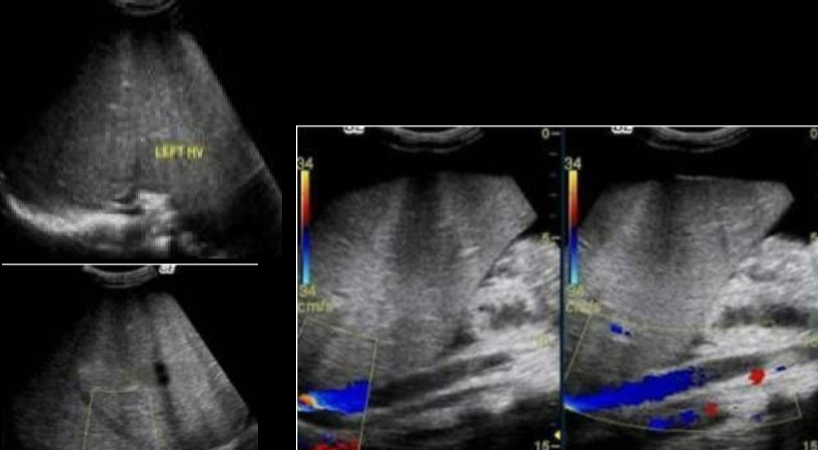

budd-chiari syndrome